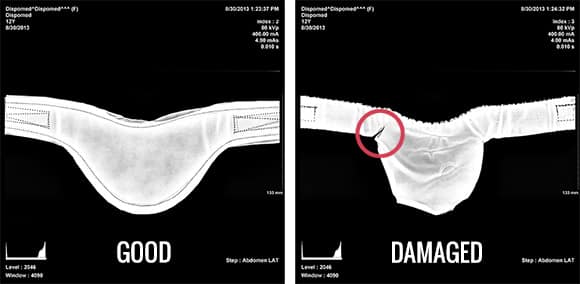

Un contrôle régulier des tabliers plombés, à l’aide d’un appareil à rayons X ou de fluoroscopie, est essentiel. Cela permet de détecter tout défaut caché, comme des fissures ou des déchirures, qui pourraient ne pas être visibles lors d’une inspection manuelle.

Comment inspecter les tabliers plombés : Principaux critères de rejet

L’inspection régulière des tabliers plombés est cruciale pour maintenir les normes de sécurité contre les radiations dans votre clinique vétérinaire. Bien qu’il n’existe pas de directives strictes de la part des gouvernements, de nombreux professionnels du secteur s’appuient sur le modèle décrit dans l’article Inspection of Lead Aprons: A Practical Rejection Model des Drs. Pillay et Stam. Voici quelques critères de rejet clés :

1. Déchirures

Les déchirures dans les tabliers plombés, en particulier celles de plus de 5,4 cm, nécessitent un rejet immédiat. Même les petites perforations autour des bords peuvent entraîner un échec, selon leur gravité. Utilisez l’imagerie par rayons X pour détecter les déchirures invisibles à l’œil nu.

Comment contrôler les tabliers plombés avec un équipement à rayons X

Les tabliers plombés sont conçus pour protéger contre les radiations secondaires (radiation diffusée), et non contre l’exposition directe au faisceau de rayons X. L’imagerie par rayons X est un moyen efficace de détecter les fissures, les déchirures ou l’amincissement du tablier. Cette méthode permet d’inspecter les défauts qui seraient difficiles à voir autrement. Bien que les tabliers plombés puissent apparaître partiellement transparents sous l’imagerie, ils restent efficaces pour bloquer la radiation diffusée lorsqu’ils sont utilisés correctement.